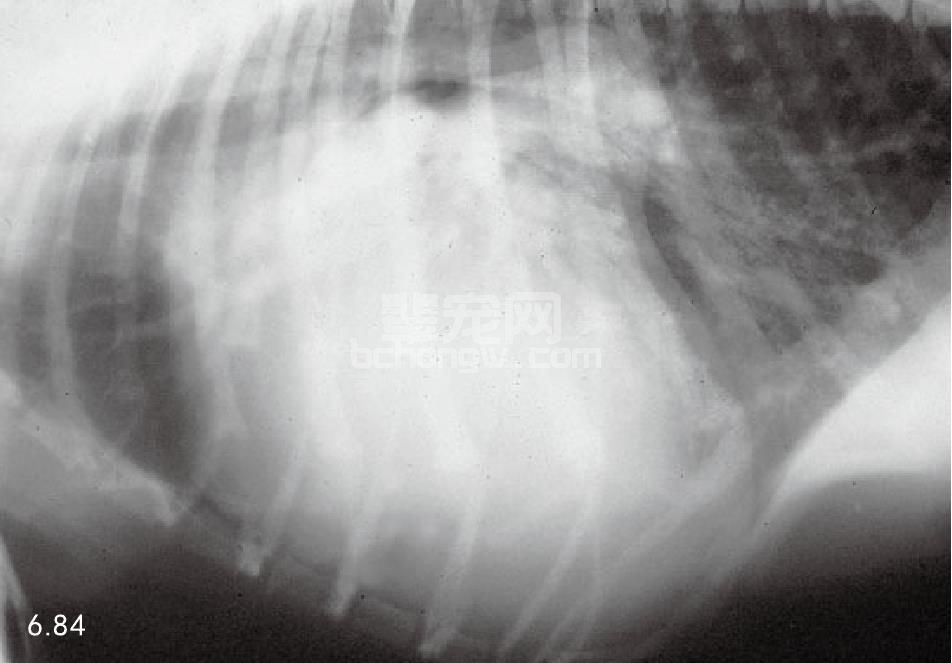

X线片 (图6.84和图6.85)有资料表明左心房和右心室于早期即开始肥大。肺部过度循环可通过肺动脉和静 脉增大而诊断,这可加速肺部水肿。在较重的病例通过背腹侧位片,可见主动脉弓、肺动脉节段以及左心耳肥 大,在12点钟和3点钟之间可见三个指节状物。

图6.84 患有PDA的5月龄标准雌性贵宾犬的胸部侧位X线片。